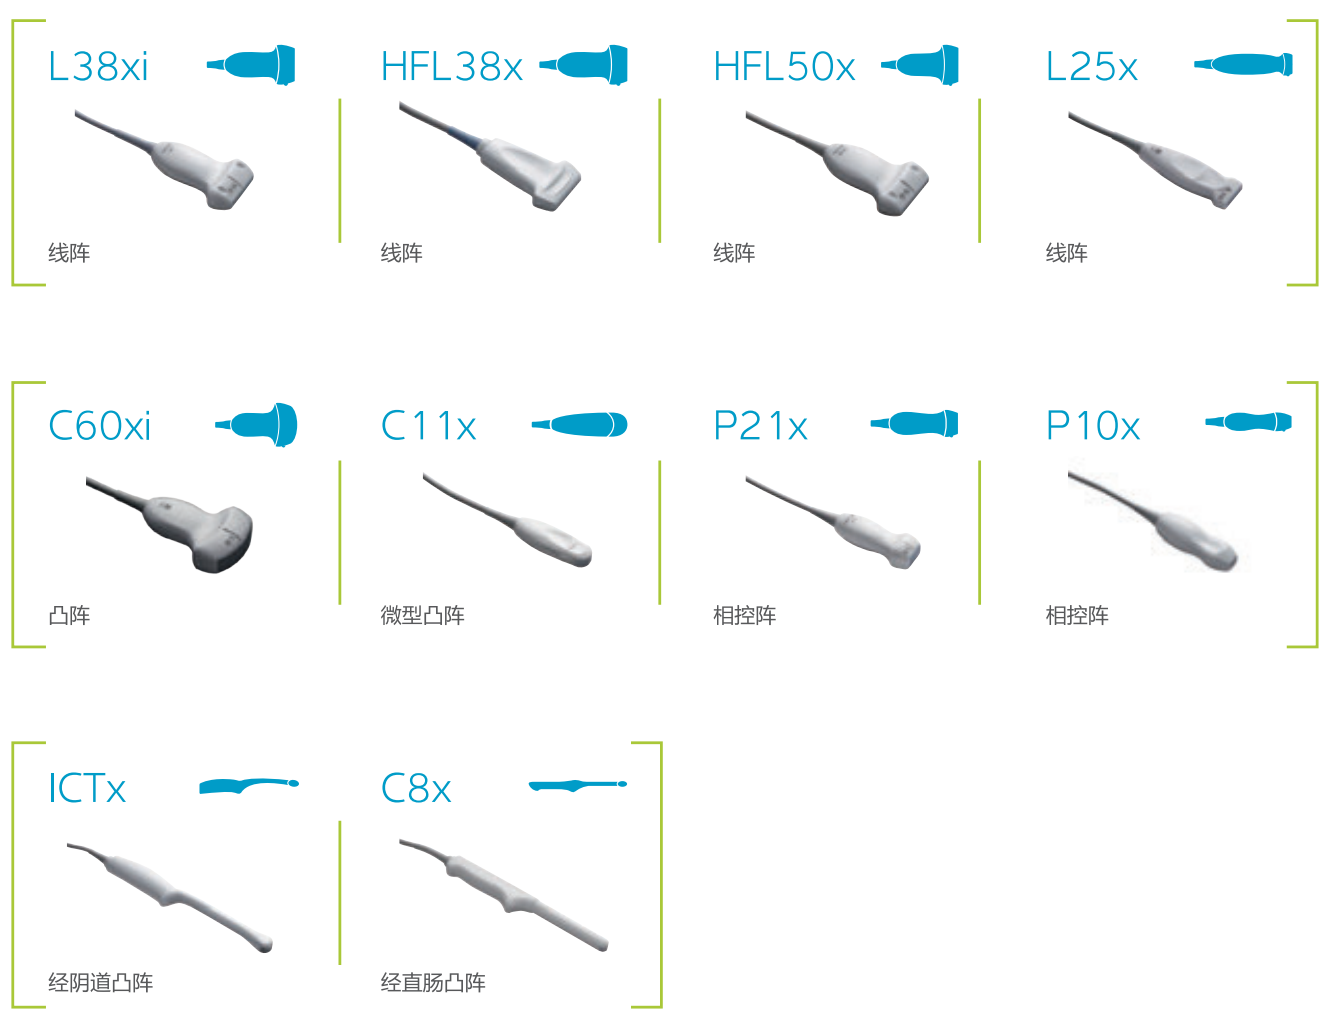

豐富的探頭群

專業(yè)POC配置